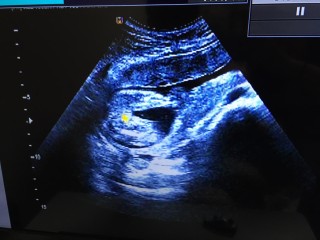

先月同様、逆子でした。性別は女の子かもしれないとのことでした! また、4Dで我が子の首にヘソの緒が。先生は何も言わなかったから 平気なんでしょうが不安でたまりません。 胎動が心配。